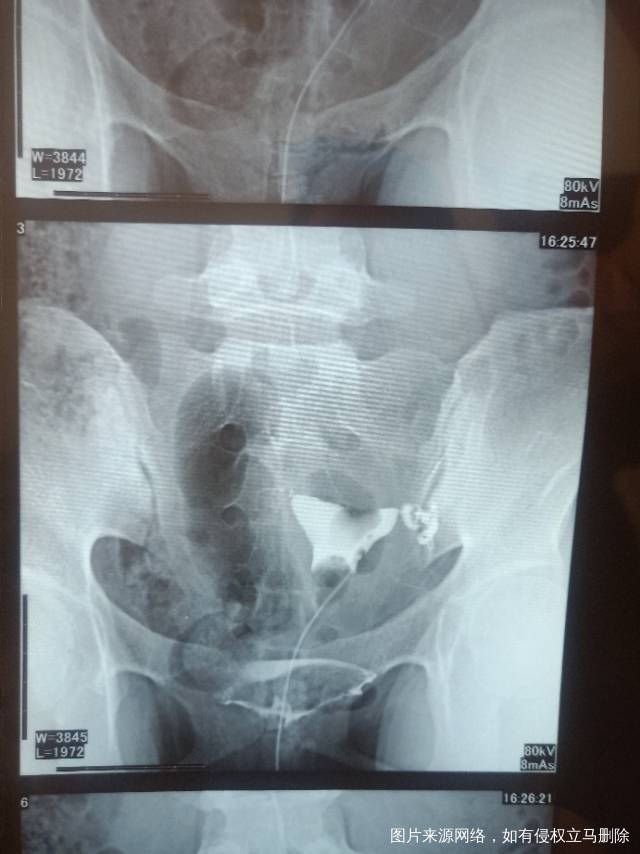

请问医生我这个造影有没有输卵管积水呀影不影响